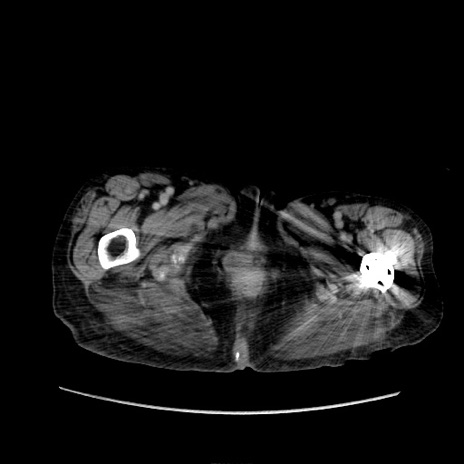

症例31(横断像)

【症例】80歳代 女性

【主訴】腹部膨満感

【現病歴】他院にて肝硬変にてフォロー中。1週間前から便秘、腹部膨満感、臍部腫瘤あり受診となる。

【既往歴】肝硬変

【身体所見】腹部膨隆あり、皮膚変化なし、疼痛なし。

【データ】WBC 4600、CRP 0.25